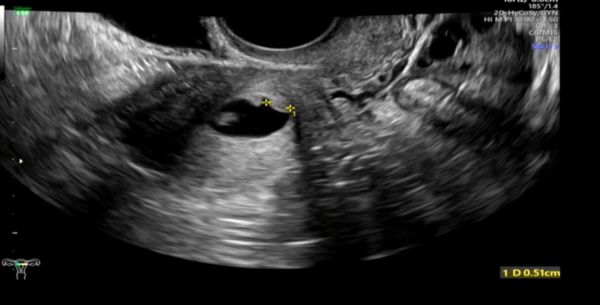

右侧输卵管积水